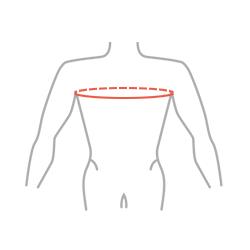

| Размер | Окружность грудной клетки | Способ снятия мерки |

|---|---|---|

| 1 | 40 — 50 см |  |

| 2 | 50 — 60 см | |

| 3 | 60 — 70 см |

ВНИМАНИЕ! Правильный размер подбирается исходя из измерения окружности груди на уровне подмышек.